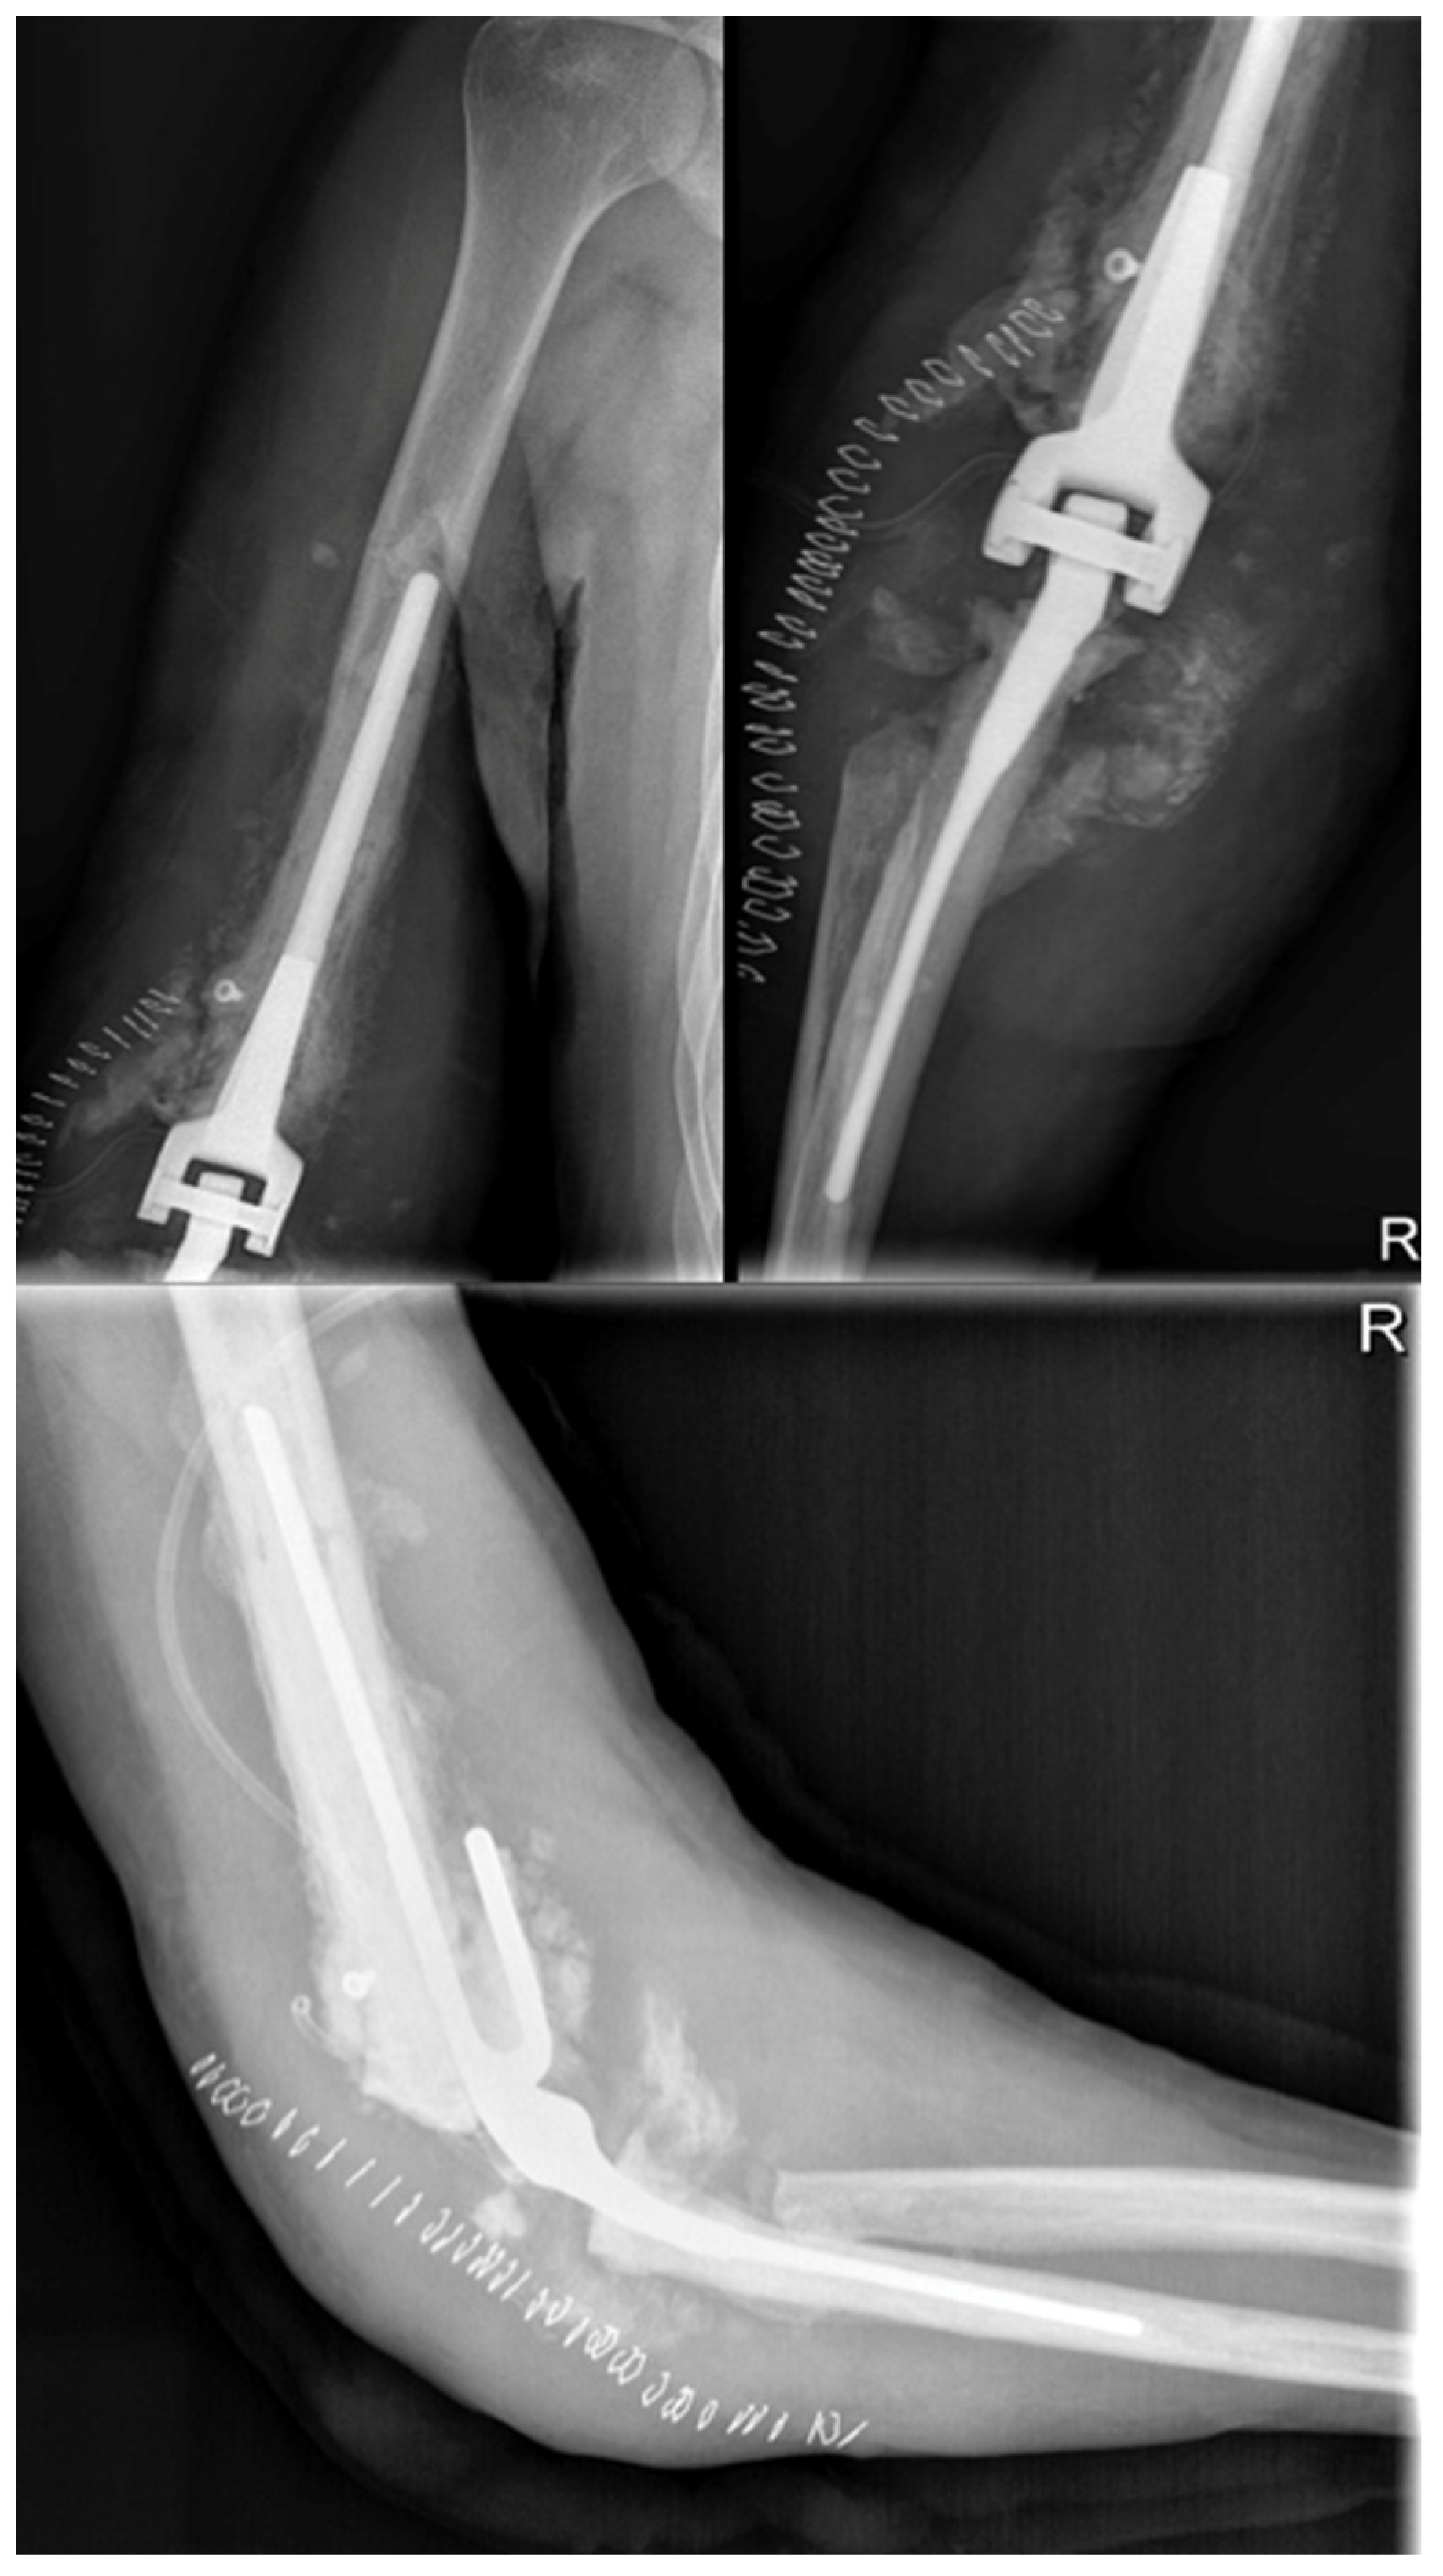

2.4.5.1. Total Elbow Arthroplasty and Complications

The patient experienced problems two months after the TEA surgery in February 2014, despite having good elbow flexion (about 120 degrees). Calcific stores had increased and a faint radio-transparent line was observed around the prosthetic humeral stem, while findings for the ulnar stem remained unchanged. A subsequent X-ray taken 15 days later revealed loosening of the humeral portion of the TEA, increased radio-transparency both at the apex and along the stem, and caudal dislocation relative to the bone, with many calcific stores being resorbed (Figure 7a). In addition, the patient was hospitalized for a recurrence of Hodgkin's lymphoma and presented with local swelling, along with increased inflammation markers including ESR at 41, CRP at 7.68 mg/dl, and white blood cells (WBC) at 10.06 thousand/mm3.

After the patient's elbow became swollen and hot with limited ROM and an audible click, an open elbow cast was applied, a blood culture was taken, and empiric antibiotic therapy with Trimethoprim/sulfamethoxazole (160mg/800mg) and Minocycline (100mg) was initiated. However, a follow-up X-ray after 15 days showed an increase in joint calcifications and no improvement in the loosening of the implants (Figure 7b).

Figure 7. (a) February 2014 X Ray anteroposterior and lateral views: beginning of the prosthesis loosening; (b) 30 days after with loosening of the prosthesis and increasing of periarticular calcifications.